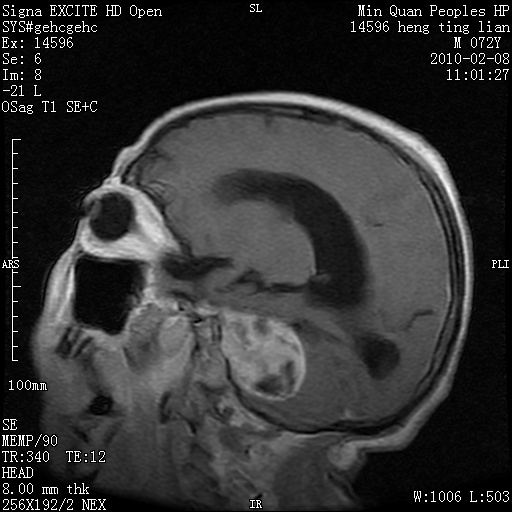

m,72,头疼,头晕两年,伴视力模糊三月,饮食呛咳两天。pe:颈部抵抗,左眼突出,左眼瞳孔约3mm,对光反射消失,双眼失明,伸舌困难,双肺呼吸音粗,心率110次/分,左上肢肌力i级,左下肢屈曲,肌张力高。现有08年2月19mri平扫及10年2月8日mri增强请会诊。ct病灶呈低密度伴散在点、片状等密度区,无明确钙化(无ct片资料可供上传)。[

脑外肿瘤,囊实性,环状不规则强化,内听道扩大,考虑神经源性肿瘤

左侧桥小脑区占位伴梗阻性脑积水----考虑 1神经鞘瘤 2室管膜瘤。

左侧桥小脑区神经鞘瘤伴梗阻性脑积水。

左侧桥脑小脑角区肿瘤并脑积水,考虑听神经瘤,脑膜瘤?

左侧桥脑小脑角区肿瘤并脑积水,考虑听神经瘤,